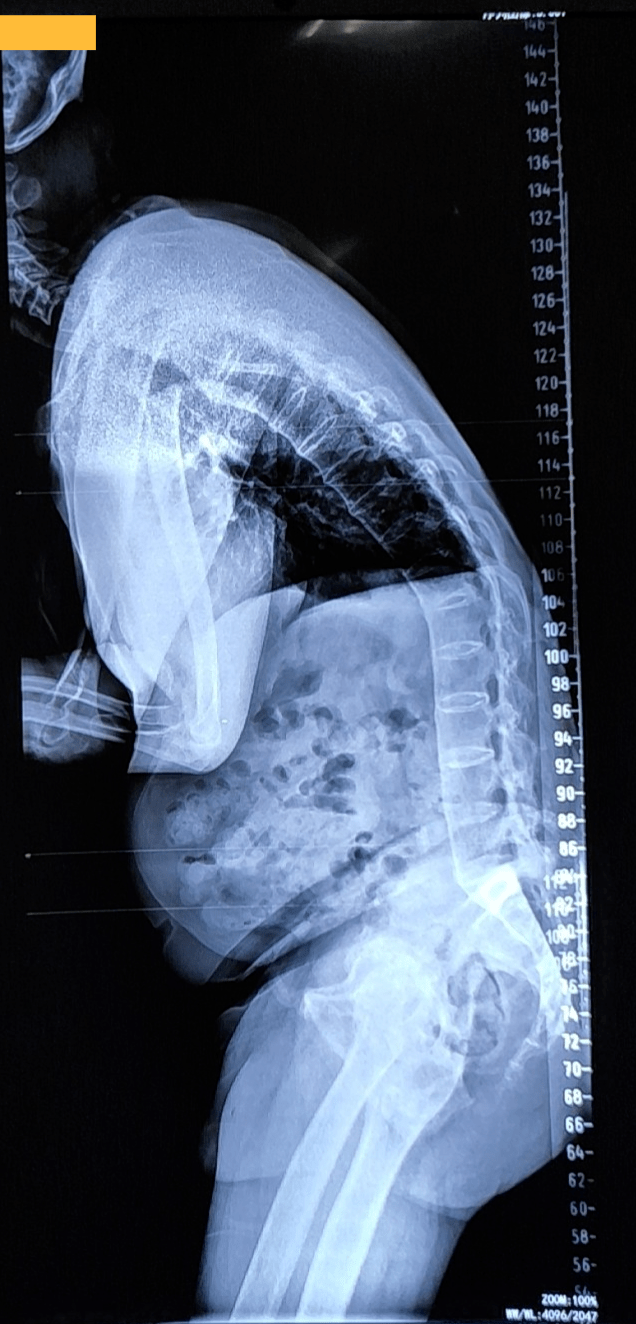

驼背x光图

从x光胸椎侧位片上看,她的驼背程度达到了中重度.